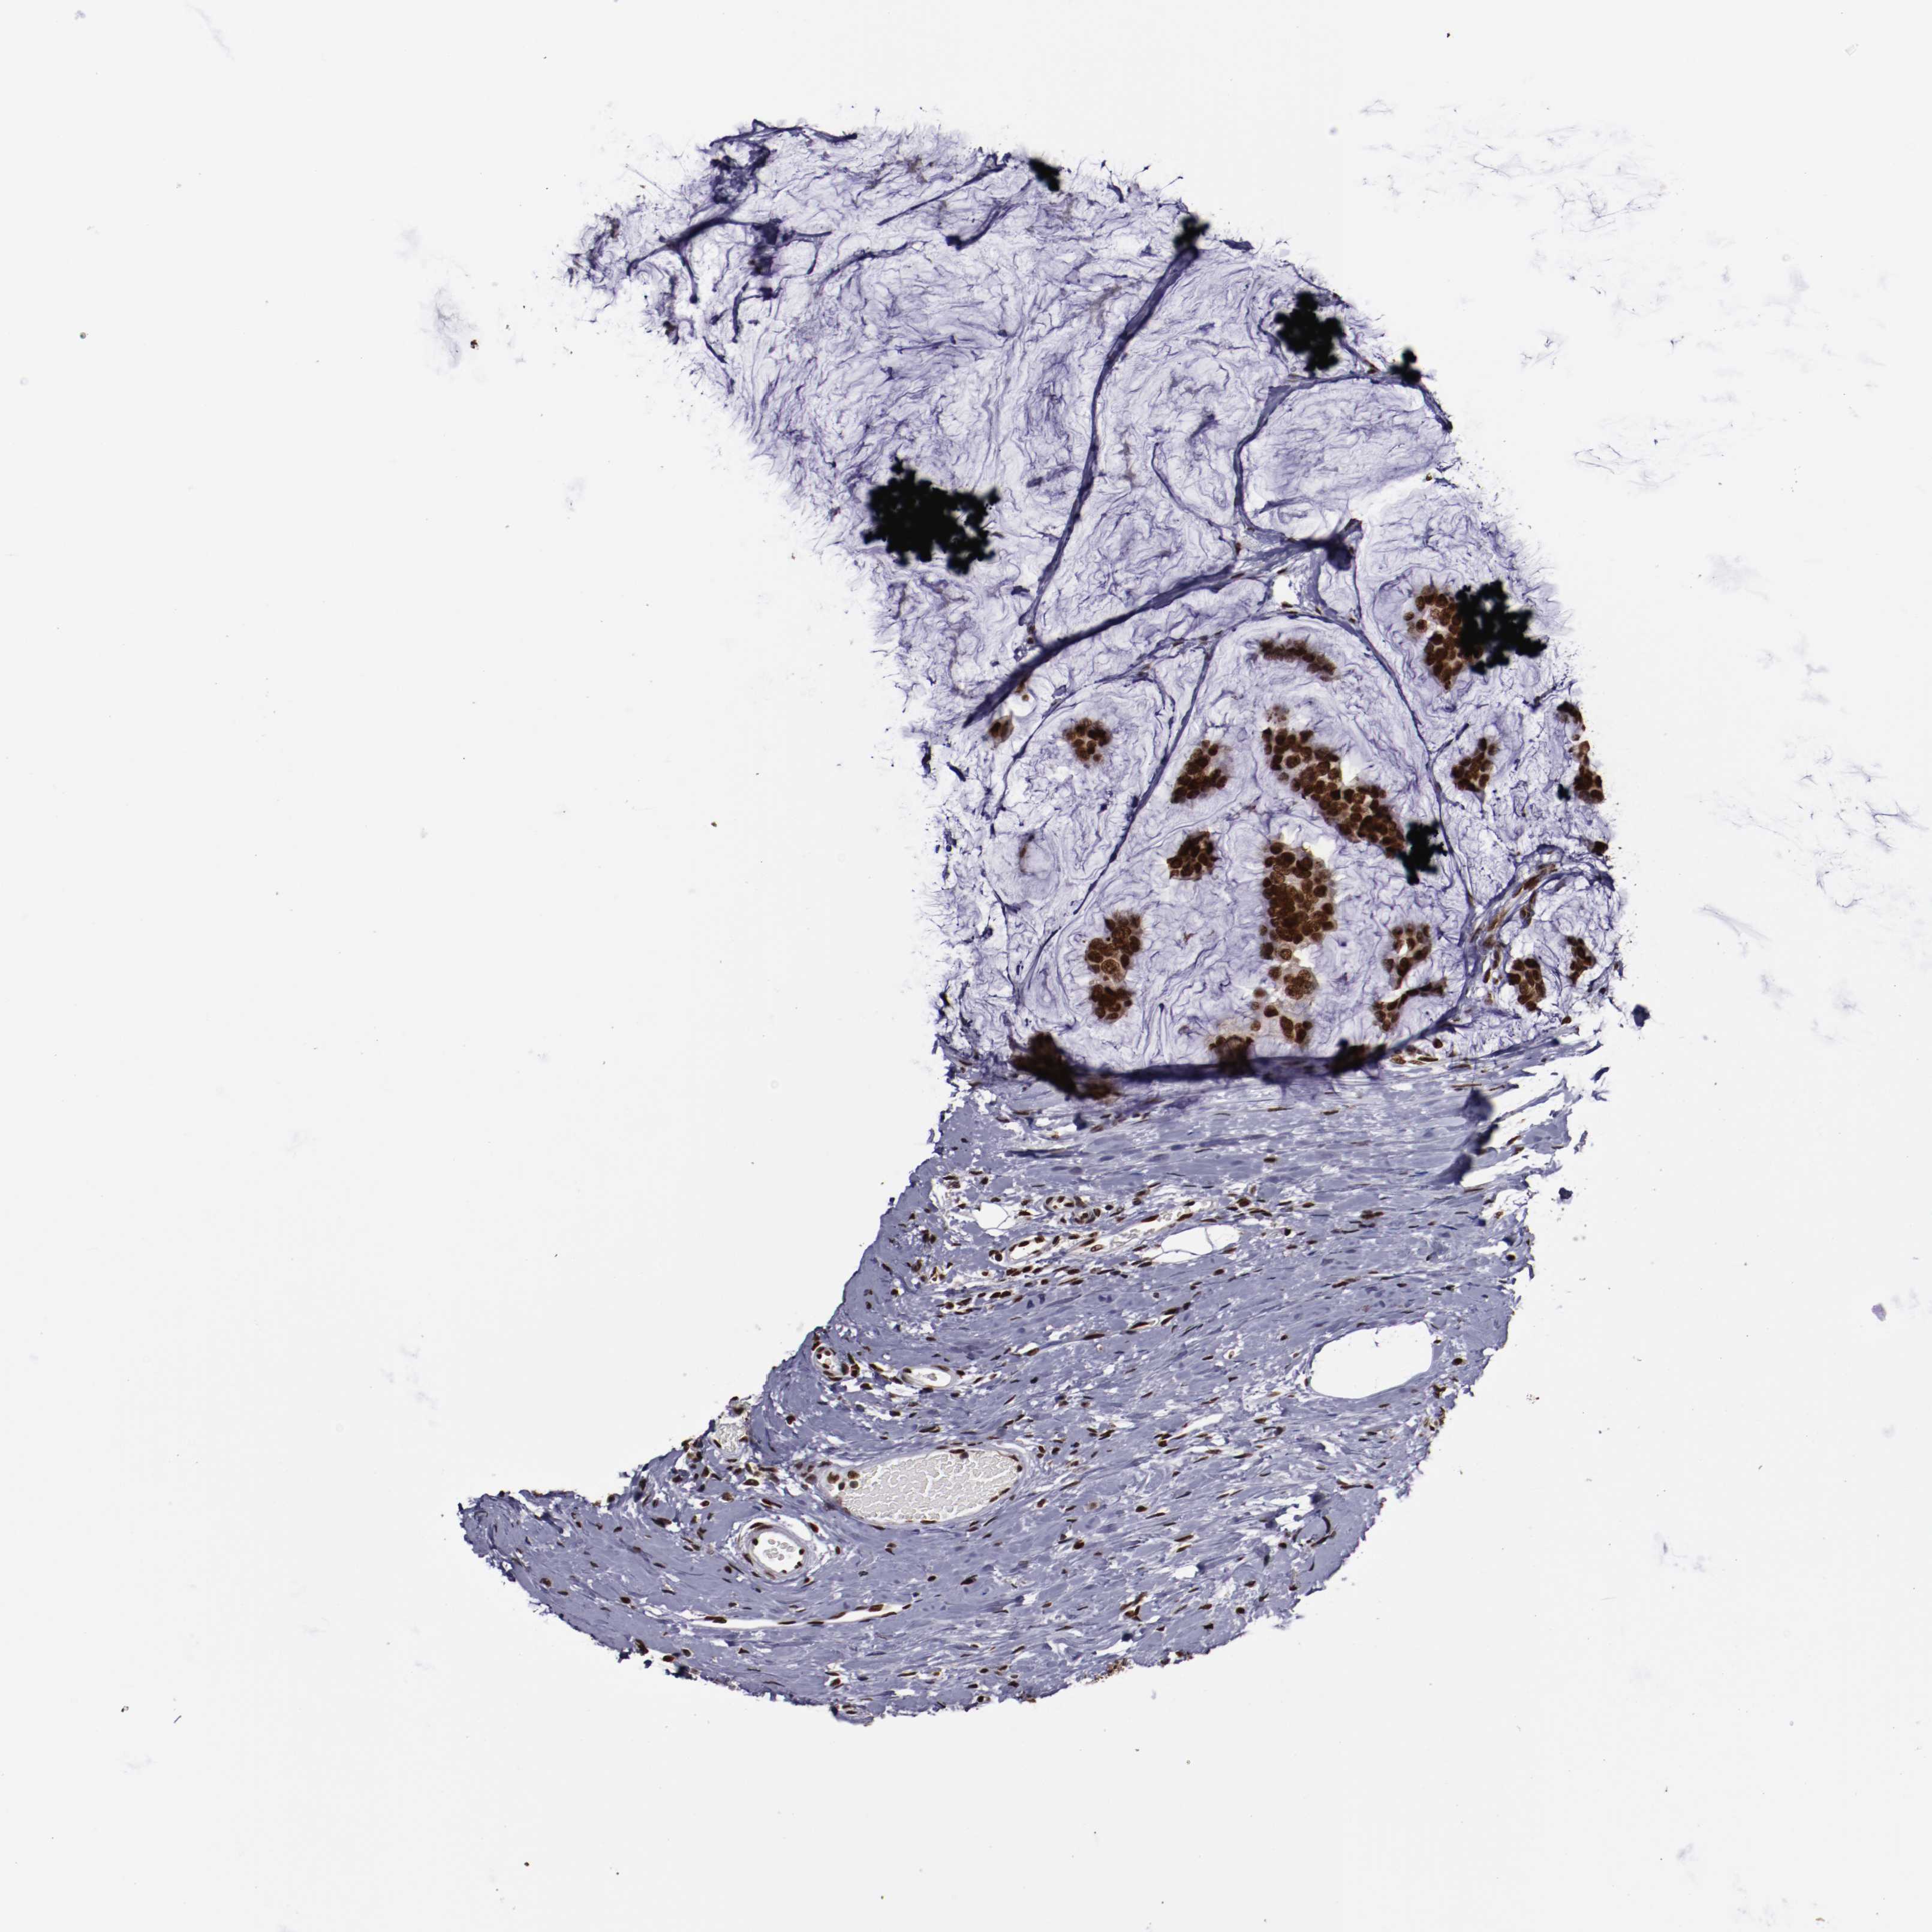

CANCER BREAST CANCER Show tissue menu

BRCA TCGA BRCA VALIDATION PROTEIN EXPRESSION

ANTIBODIES

AND

VALIDATION